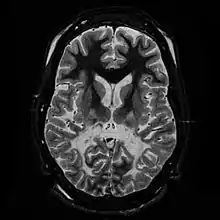

| T2 weighted axial scan of a human brain at the level of the caudate heads demonstrates marked loss of posterior white matter, with reduced volume and increased signal intensity. The anterior white matter is spared. Features are consistent with X-linked adrenoleukodystrophy. | |

When damage occurs to white matter, subsequent immune responses can lead to inflammation in the central nervous system (CNS), along with the loss of myelin. The degeneration of white matter can be seen in an MRI scan and is used to diagnose leukodystrophy. Leukodystrophy is characterized by specific symptoms, including decreased motor function, muscle rigidity, and eventual degeneration of sight and hearing. While the disease is fatal, the age of onset is a key factor, as infants have a typical life expectancy of 2–8 years, while adults typically live more than a decade after onset. Treatment options are limited, although hematopoietic stem cell transplantations using bone marrow or cord blood seem to help in certain leukodystrophy types, while further research is being done.

The degeneration of white matter, which reflects the degeneration of myelin, can be seen in a basic MRI and used to diagnose leukodystrophies of all types. T-1 and T-2 weighted fluid-attenuated inversion recovery (FLAIR) images are the most often used approach.[24] Electrophysiological and other kinds of laboratory testing can also be done. In particular, nerve conduction velocity is looked at to distinguish between leukodystrophy and other demyelinating diseases, as well as to distinguish between individual leukodystrophies. For example, individuals with X-ALD have normal conduction velocities, while those with Krabbe disease or metachromatic leukodystrophy have abnormalities in their conduction velocities.[24] Multigene sequencing panels for undifferentiated leukodystrophy are offered for rapid molecular diagnosis after genetic counselling.